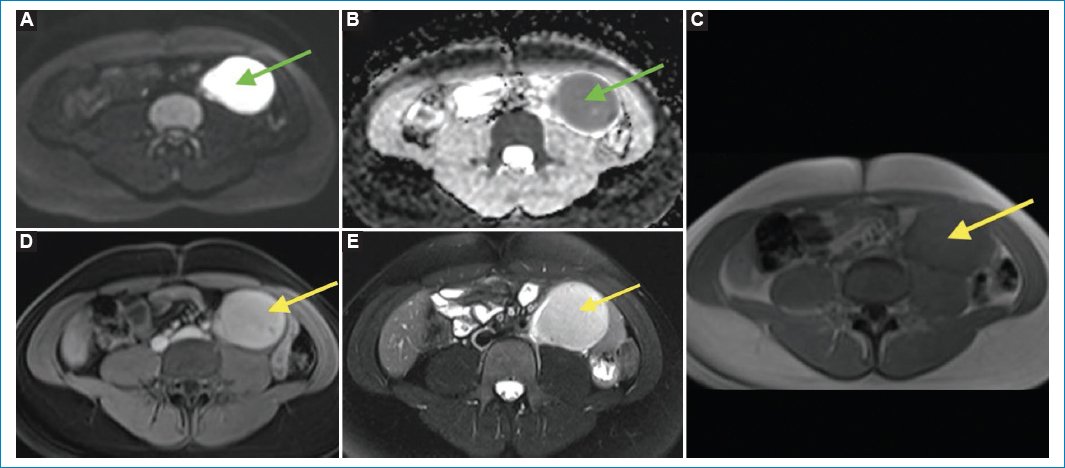

Se trata de una mujer de 25 años con antecedente de hipotiroidismo que consultó por una masa palpable en el mesogastrio, sin dolor ni otros síntomas gastrointestinales. Se realizó ecografía de abdomen que mostró una masa sólida, retroperitoneal, paraaórtica izquierda, adyacente al músculo psoas. Se complementó entonces con tomografía computada (TC) de abdomen contrastada, encontrando una masa de 8 × 5,6 cm, con realce homogéneo con el medio de contraste, sin zonas de necrosis ni calcificaciones, sin invadir las estructuras adyacentes y en estrecha relación con el músculo psoas (Fig. 1). Se solicitó una resonancia magnética (RM) contrastada para mejor caracterización. Dicha masa presentaba intensidad de señal homogénea, isointensa en T2, hipointensa en T1, con restricción a la difusión (alta señal en el DWI y baja señal en el ADC), y realce temprano homogéneo e intenso con el medio de contraste (Fig. 2), asociado a varios ganglios retroperitoneales. Se sugirió como primera posibilidad linfoma retroperitoneal. Se realizó biopsia y resección de ganglio retroperitoneal, con reporte de patología de enfermedad de Castleman hialinovascular.

Figura 2. RM contrastada en secuencias DWI (A) y mapa ADC (B), T1 pre- y posgadolinio (C y D), y T2 con saturación grasa (E). La masa retroperitoneal tiene intensidad de señal homogénea, es hiperintensa en las secuencias ponderadas en T2 (E, flecha amarilla) e isointensa al músculo en las secuencias ponderadas en T1 precontraste con realce homogéneo con el gadolinio (C y D, flechas amarillas), y presenta marcada restricción de la difusión (A y B, flechas verdes).